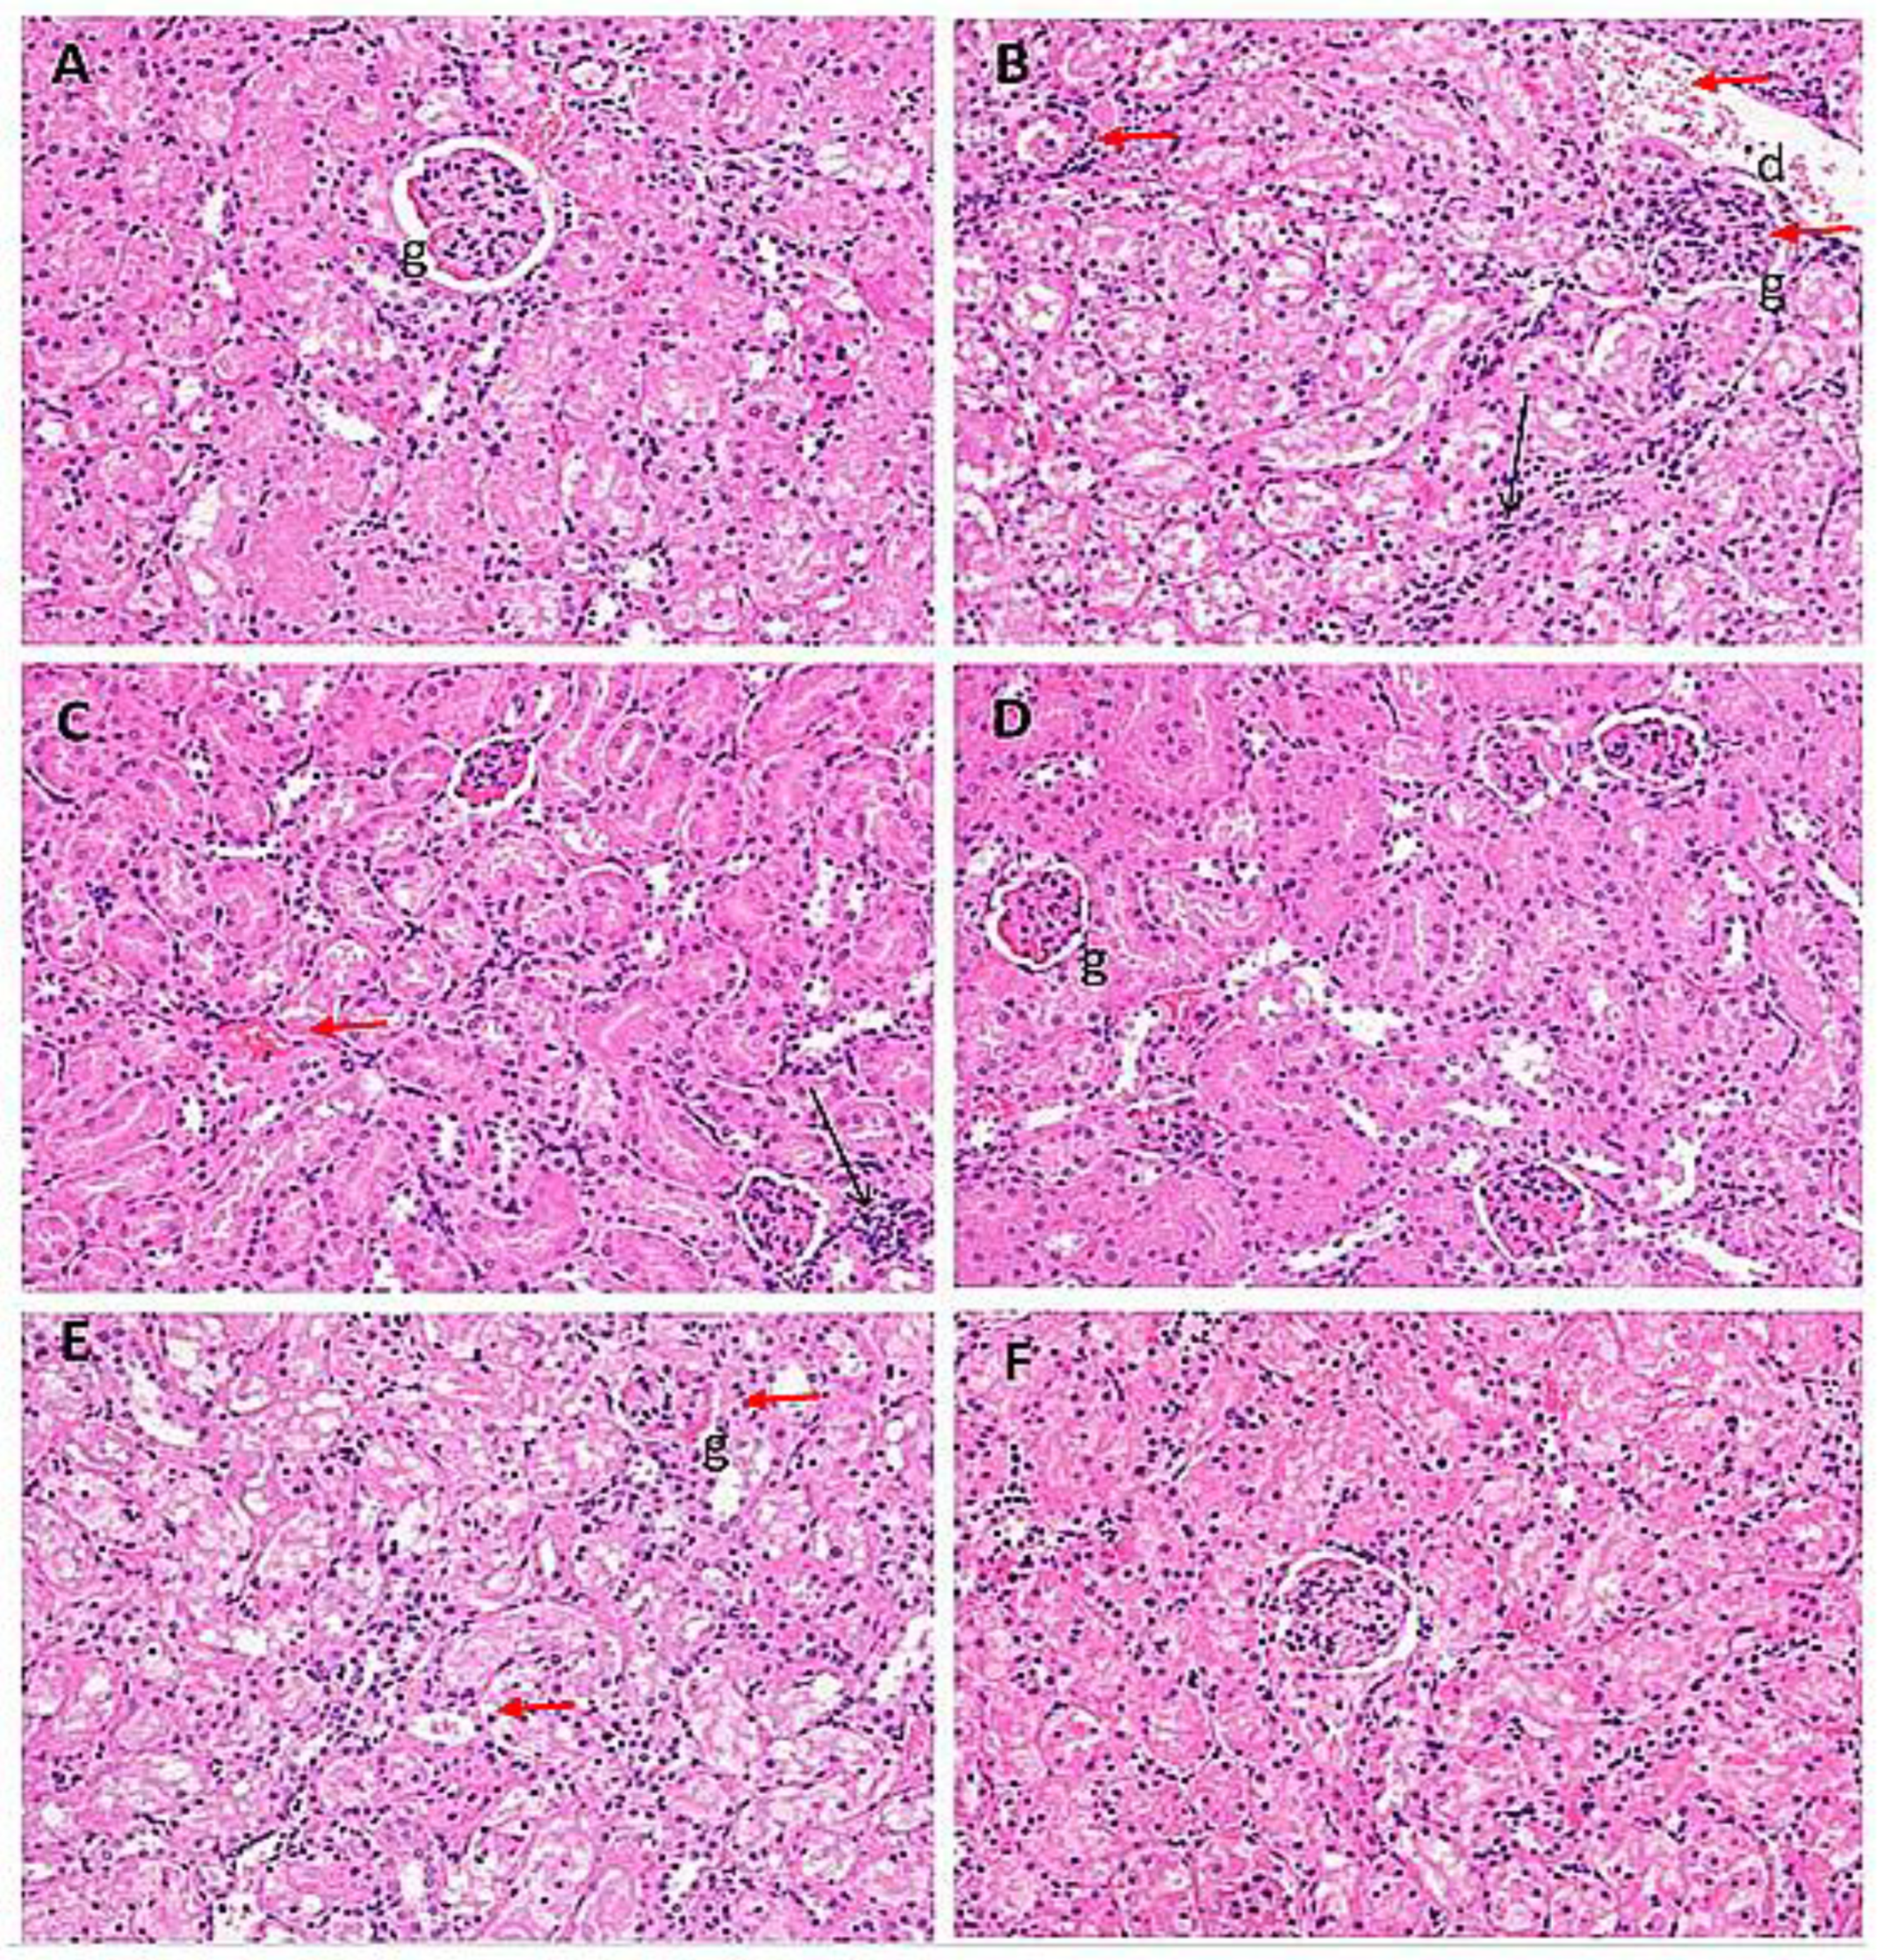

2.7. Histological Evaluation of Kidney Samples

| Treatment Groups | I | II | III | IV | V | VI |

|---|---|---|---|---|---|---|

| Oedematous glomeruli | − | +++ | ++ | − | +++ | − |

| Hemorrhage | − | ++ | ++ | − | − | − |

| Infiltration of inflammatory cells | − | +++ | ++ | + | ++ | + |

| Hyaline casts | − | ++ | ++ | − | ++ | + |

| Disintegrated nucleus | − | + | − | − | − | − |